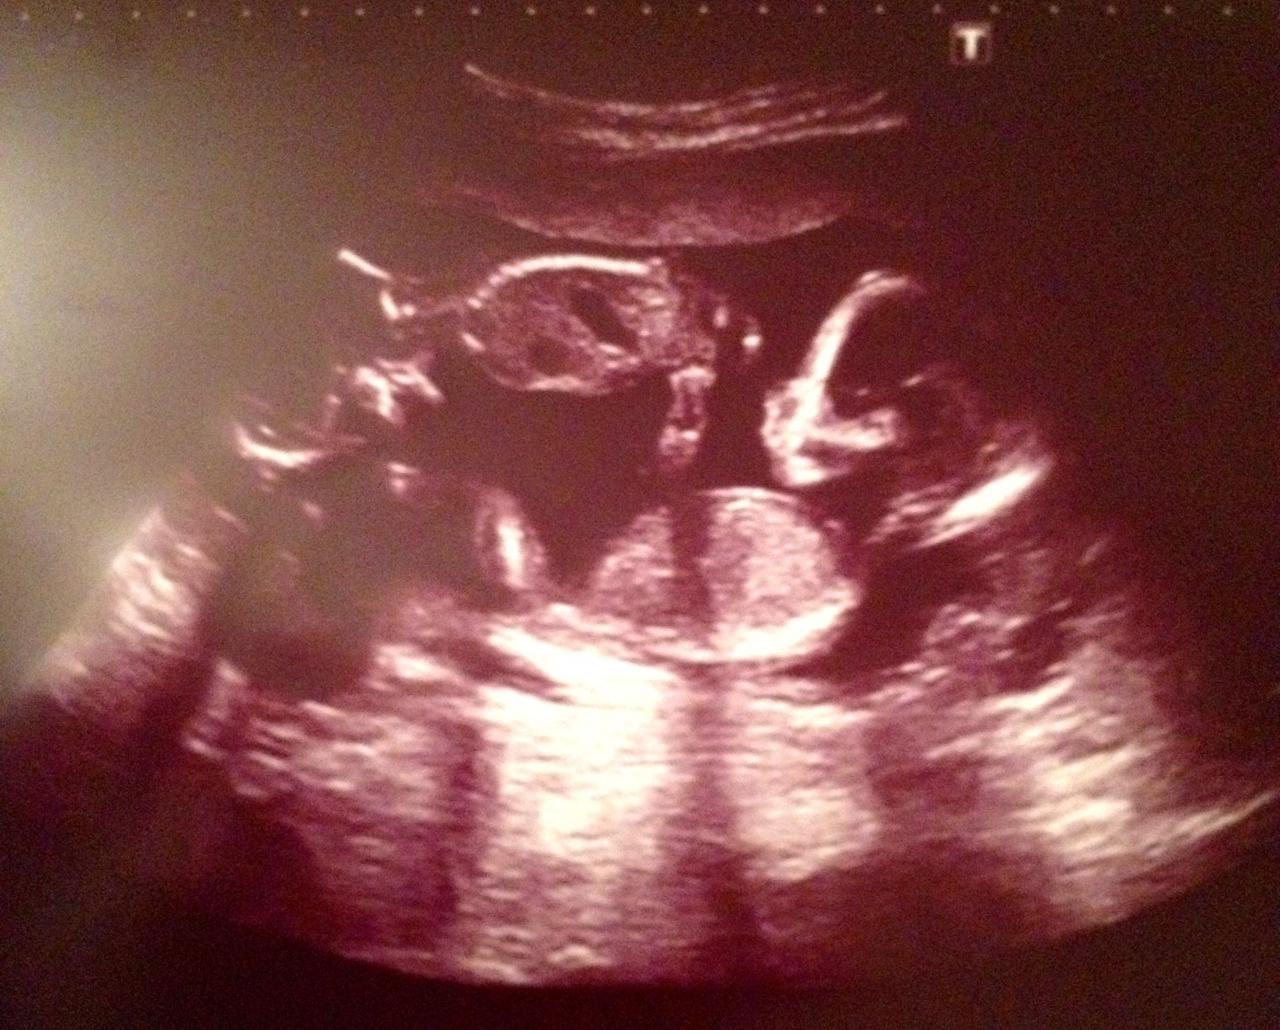

Hier ein Foto von meinen zwei Mädels.